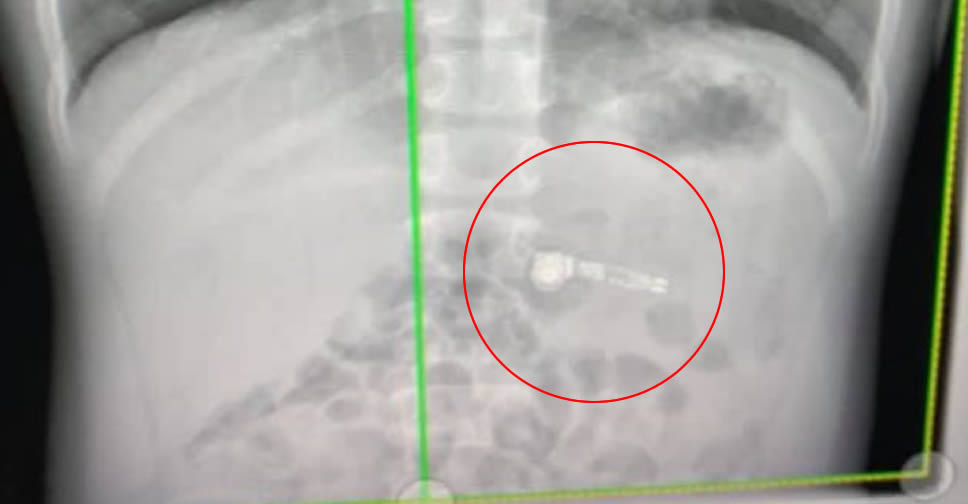

Kiara Stroud คุณแม่ของเด็กชายวัย 7 ขวบ พบว่าลูกของเธอได้เผลอกลืน AirPods ลงไป จึงได้รีบนำตัวส่งโรงพยาบาล โชคดีที่ไม่ติดคอ ซึ่งอาจเป็นการสูญเสียครั้งใหญ่ และหลังจากผ่านการเอ็กซเรย์ ก็พบว่ามี AirPods ข้างหนึ่งอยู่ในท้องของเด็ก

คุณหมอที่ได้เห็นภาพเอ็กซเรย์ ยืนยันว่าลูกชายวัย 7 ขวบของ Kiara Stroud กลืน AirPods ลงไปในปากจริงๆ และหวังว่าเด็กจะสามารถขับถ่าย AirPods ออกมาได้เอง โดยไม่ต้องทำการผ่าตัดใดๆ